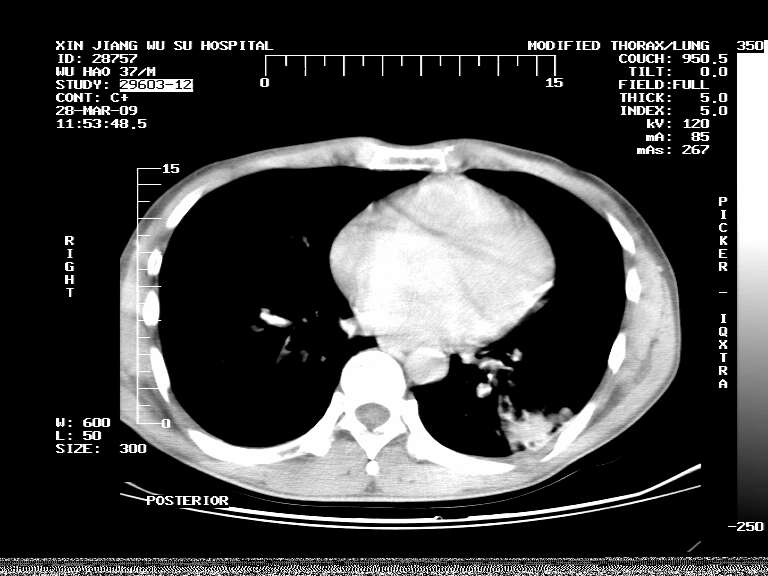

男,37岁,体检胸透发现阴影。

患者体检发现 无症状 左肺下叶占位,边缘模糊,可见血管聚束、分叶、胸膜牵拉,增强呈不均匀性强化。 首先考虑左肺下叶周围型肺癌,建议穿刺活检。

患者体检发现 无症状 左肺下叶占位,边缘模糊,可见血管聚束、分叶、胸膜牵拉,增强呈不均匀性强化。 首先考虑左肺下叶周围型肺癌,建议穿刺活检。支持!

左肺下叶见一结节病变,边缘欠清不光滑,与胸膜粘连且胸膜局限性增厚,注药后呈环形强化,动脉期壁呈明显点环状强化,静脉期壁强化减低,中心密度低无强化,灶周无明显的卫星灶和水肿区(晕征)---考虑周围性肺癌,不除外感染性病变,建议穿刺活检。

左肺下叶软组织病灶,密度较高,内见点状钙化,其周围见子灶,邻近胸膜扁平样增厚.c+病灶强化明显,中心强化弱.诊断:左肺下叶结核瘤.

左肺下叶大片实变影,内靠胸膜见不规则更高密度结节灶,边缘强化,相邻胸膜增厚,胸膜下脂肪线存在。考虑炎症,结核可能。